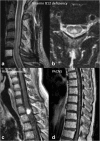

Purpose: Miliary enhancement refers to the presence of multiple small, monomorphic, enhancing foci on T1-weighted post-contrast MRI images. In the absence of a clear clinical presentation, a broad differential diagnosis may result in invasive procedures and possibly brain biopsy for diagnostic purposes.

Methods: An extensive review of the literature is provided for diseases that may present with miliary enhancement on T1-weighted brain MR images. Additional disease-specific findings, both clinical and radiological, are summarized and categorized by the presence or absence of perivascular space involvement.

Results: Miliary pattern of enhancement may be due to a variety of underlying causes, including inflammatory, infectious, nutritional or neoplastic processes. The recognition of disease spread along the perivascular spaces in addition to the detection or exclusion of disease-specific features on MRI images, such as leptomeningeal enhancement, presence of haemorrhagic lesions, spinal cord involvement and specific localisation or systemic involvement, allows to narrow the potential differential diagnoses.

Conclusion: A systematic approach to disease-specific findings from both clinical and radiological perspectives might facilitate diagnostic work-up, and recognition of disease spread along the perivascular spaces may help narrowing down differential diagnoses and may help to minimize the use of invasive diagnostic procedures.